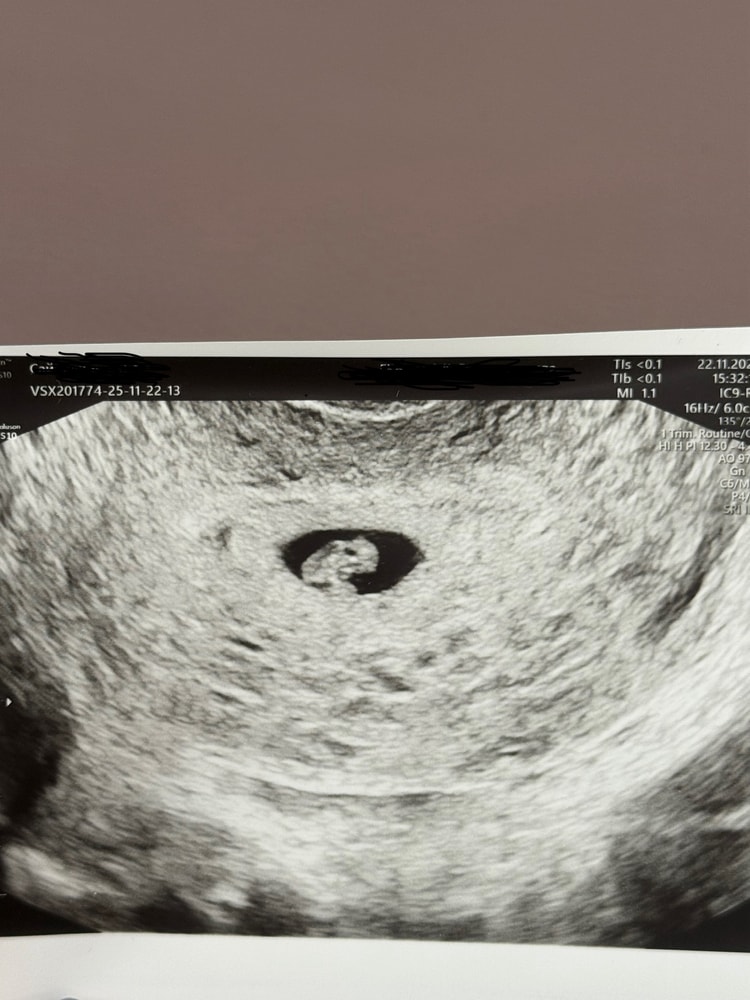

Нам 6 недель 4 дня)))

УЗИ, КТГ, доплерПрилагаю фото 6 недель 4 дня,может кому-то интересно как и что выглядит на таком сроке, сб+ 108 ударов в минуту, эмбриончик 6,5мм желточный мешок 3мм, плодное яйцо 15мм.